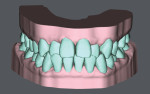

30-year-old female patient presented complaining of being embarrassed and insecure about her smile. Upon examination, the patient exhibited poor oral hygiene, bleeding, deep pockets, bone loss, and heavy subgingival and supragingival calculus. There was moderate-severe crowding in her maxillary arch with severe anterior cross-bite on teeth Nos. 7 and 10. A comprehensive treatment plan was presented and included stabilizing her periodontal condition and proceeding with SureSmile® Clear Aligners (Dentsply Sirona, suresmile.com) therapy. Clear aligner therapy was indicated over traditional brackets and wires due to hygiene concerns and the patient's existing periodontal condition. The case was completed with 35 aligners, attachments, and the adjunctive use of Chewies aligner tray seaters and SureSmile® VPro™, which were included in the SureSmile Complete package. The SureSmile aligner straight trimline design over the gingiva allowed for excellent traction and retention and minimal attachments. The patient experienced no gingival discomfort and tolerated the treatment well. Her smile was aligned to completion in 11 months with good traction and without refinement. The patient's periodontal condition and oral hygiene were improved with the overall effect of treating malocclusion. Today, the patient is proactive about her oral health, exhibits a confident, healthy smile, and is currently in retention therapy with SureSmile retainers.

SureSmile Clear Aligners therapy was able to predictably treat a moderate to severe anterior cross-bite case with minimal aligners and attachments, in a relatively short time period without refinement.